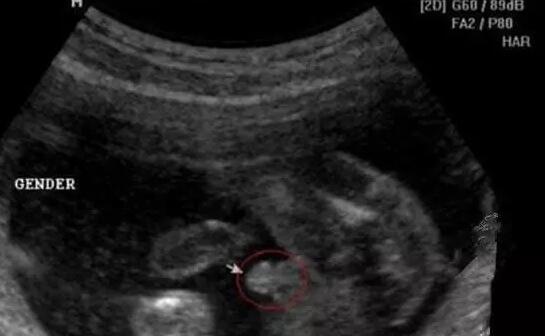

四维彩超男宝宝特征如下

男宝宝如何通过B超分辨出来呢,其实也很简单了,如果角度合适,男宝的B超图上是可以看到小丁丁的。下图拍摄取的角度就是宝宝屁屁正下方,一目了然。

小丁丁